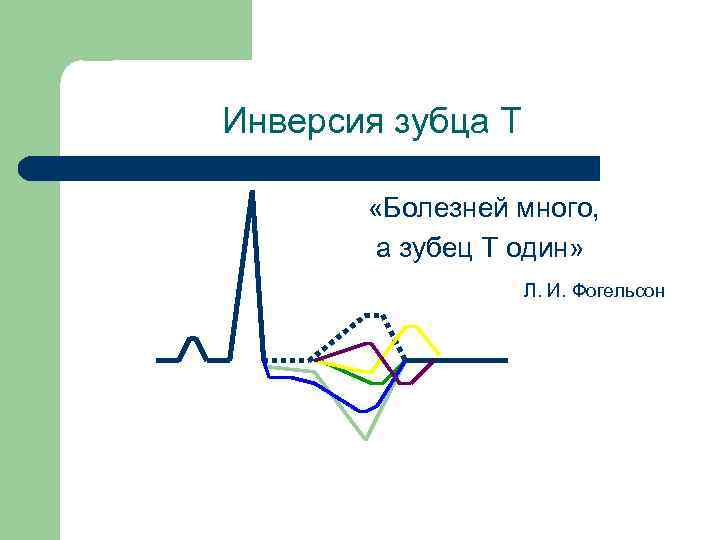

Инверсия зубца Т «Болезней много, а зубец Т один» Л. И. Фогельсон